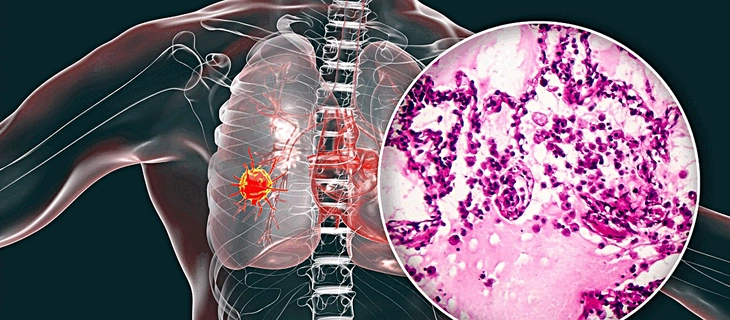

Kết quả chẩn đoán năm 1998, ông Whitney mắc bệnh ung thư phổi không phải tế bào nhỏ ở giai đoạn 4 (giai đoạn cuối) với tiên lượng chỉ sống được 10 tháng. Năm đó ông 65 tuổi, đang là nhà khoa học phát triển sản phẩm cho Tập đoàn Raychem tại Menlo Park (bang California, Mỹ).

Đầu tiên ông tìm hiểu mọi thứ về bệnh ung thư phổi không phải tế bào nhỏ. Ông nhận ra những gì bác sĩ nói với ông đều đúng, ông có thể chết trong vòng một năm.

Nhiều tháng hóa trị chuyên sâu, cuối cùng khối u giảm 50%. Ông đã chịu phẫu thuật cắt thùy phổi loại bỏ khối u lớn. Kế đến ông tiếp tục điều trị nhiều tháng với nhiều phác đồ hóa trị khác nhau để loại bỏ 19 khối u nhỏ phát triển sau phẫu thuật. Hầu hết khối u nhỏ đã bị loại bỏ, chỉ còn bốn khối u.

Lúc này các nhà nghiên cứu bắt đầu tìm hiểu di truyền học bệnh ung thư của ông. Họ giải trình tự gene khối u và phát hiện có một đột biến gene eGFR.

Yếu tố này giúp ông đủ điều kiện tham gia thử nghiệm loại thuốc điều trị mới mang tên Iressa (hoạt chất gefitinib) vì mục đích nhân đạo (điều trị thử nghiệm cho người mắc bệnh nghiêm trọng hoặc đe dọa tính mạng). Hằng ngày ông cũng dùng thuốc celebrex (celecoxib) để điều trị đau và viêm.